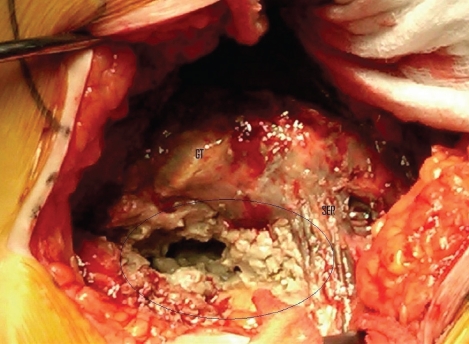

Most likely the cause is from the friction and rubbing together of the two metal surfaces of your hip implant. Small dust-like particles of the metals sheer off and spread through your body via your bloodstream. During revision surgery, doctors are finding dark discolored fluid and dead tissue in the body’s joint area surrounding the metal on metal hip. All patients with recalled metal on metal hip replacements should be evaluated for the level of serum cobalt and chromium in their system.